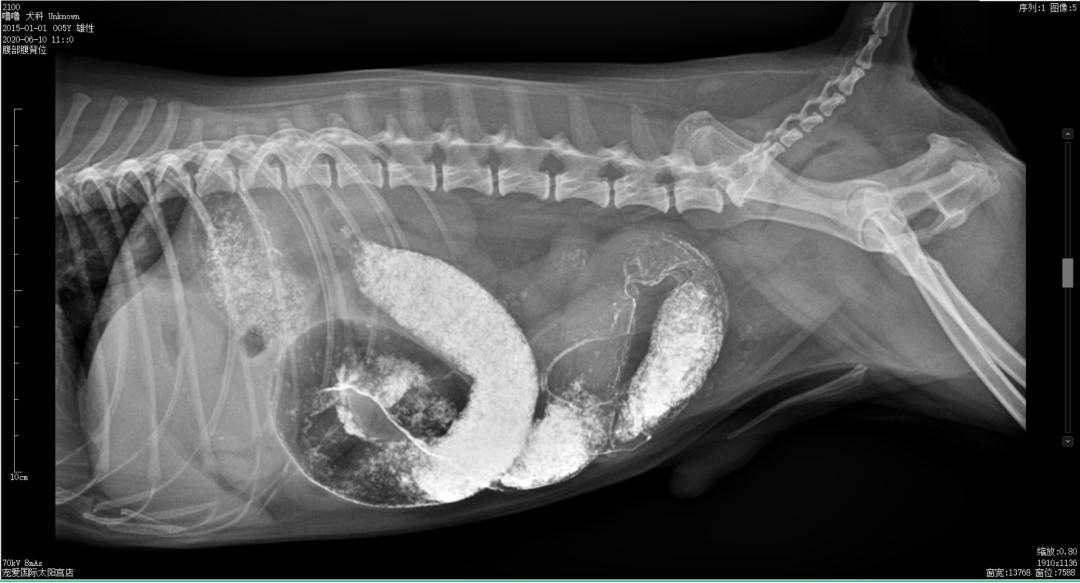

钡餐造影

常规打开腹腔,发现肠道因气体而扩张,找到异常肠道发现异物位于空肠内,在异物远端外健康肠组织处切口,用手术刀或者手术剪延肠管长轴打开切口,以便取出异物但不会撕裂肠道,取出异物后,修整外翻黏膜层边缘使其与浆膜层对齐,纵向或者横向对接切口,进行全层简单间断缝合,在距边缘2mm处全层缝合肠壁,进针时全层穿透轻轻上挑针尖并退针至黏膜层滑出,在从对侧黏膜-黏膜下层结合层进针,进针前针尖轻轻下压使黏膜层内翻,小心系紧每根缝线,不要切割肠壁层,轻轻对接不要压碎组织。缝线选择优选可吸收单丝线(多丝线阻力大,吸渗作用大,炎症反应大),如果动物ALB<2g/dL时,可以考虑使用不可吸收单丝线,再以大网膜覆盖于肠切口的周围,关闭腹腔,缝合皮肤。